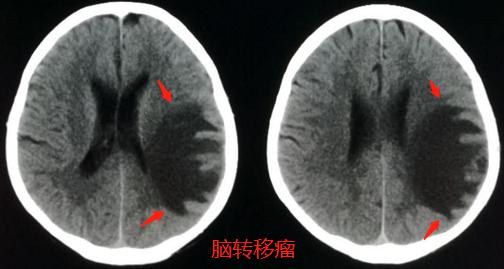

病例1,男性65,言语不清5天,怀疑脑血栓做了脑CT检查:

左顶叶巨大低密度水肿区,不按供血区分布,在脑灰白质交界区似乎有小结节,不符合脑梗死,首先考虑脑转移瘤。

怀疑脑转移,首先要查肺部CT(肺癌常见脑转移),于是肺部扫描发现了下面这个病灶:

这样就确诊了:右下肺癌脑转移。